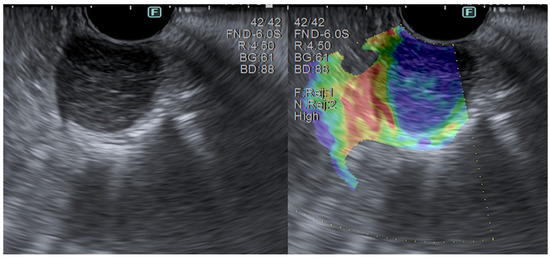

3.1. Color Doppler

3.2. Elastography

3.3. Contrast-Enhanced EUS